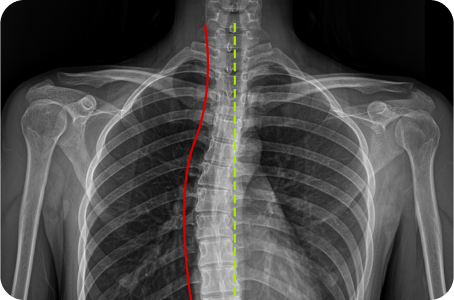

3차원 척추교정이란?

척추의 틀어진 방향과 휘어진 각도는 사람마다 모두 다릅니다.

옆, 앞, 뒤가 각자 틀어지고 꼬인 척추의 변형은 각도와 방향 모두를 고려한

3차원 척추 교정으로 바로잡아야 합니다.

정면, 측면 시각에서 틀어진 방향

척추 만곡의 각도

척추뼈 마디의 회전 변형